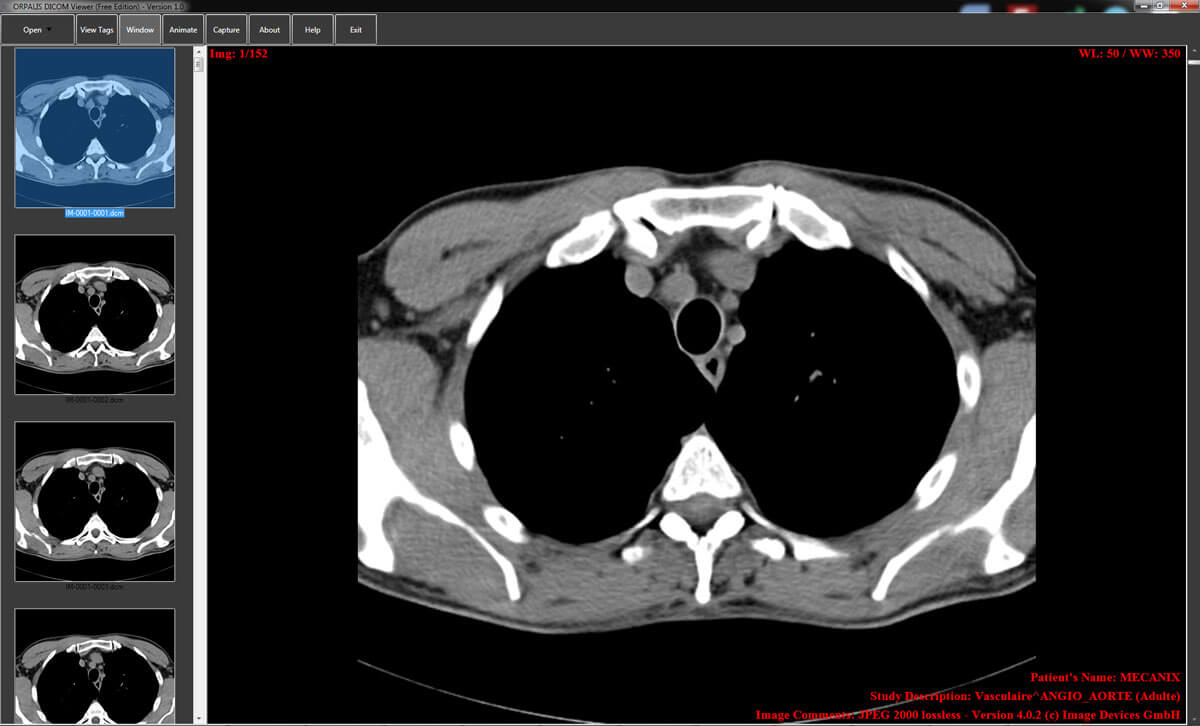

The Orpalis DICOM viewing tool supports all DICOM files and has a simple interface. There is a dedicated forum for support and problem-solving. It is capable of animating multiple frames in a loop mode for easy viewing. Images can be captured and pasted to other presentations or documents.